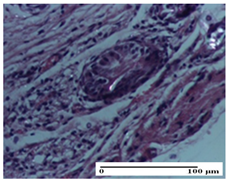

On the ninth day, for the incision-type injury, all groups treated with ointments (AP, PPo, APo, APPo) showed dermal collagenization. For the excision-type lesion, dermal collagenization was also noted, except for the AP group, which presented severe dermal collagenization that also affected the muscle plane. In the burn-type lesion, dermal collagenization was observed for all treated groups and a moderate inflammatory infiltrate was present for the APo and APPo groups (Table 5).

We found superior results on days 6 and 9, both in terms of wound contraction and re-epithelialization, with the best results being obtained with the ointment that assumed the synergistic effect of apitherapy–phytotherapy–natural polymers principles. These effects are supported, in addition, by the histological results, where, from the ninth day, for the treated groups, dermal collagenization is observed, sometimes important (AP group) or dermal collagenization with rare inflammatory elements. On day 21, dermal collagenization and restoration of histological structure occurred for all treated groups, and healing occurred without keloid scars.